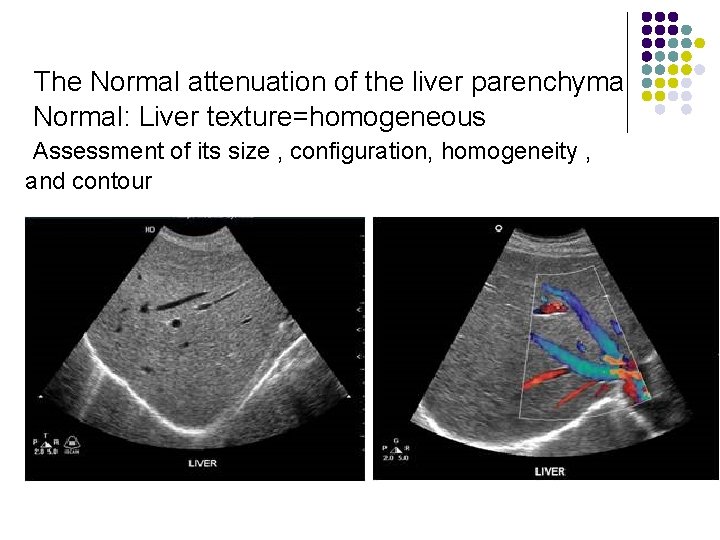

The Normal attenuation of the liver parenchyma Normal: Liver texture=homogeneous Assessment of its size , configuration, homogeneity , and contour